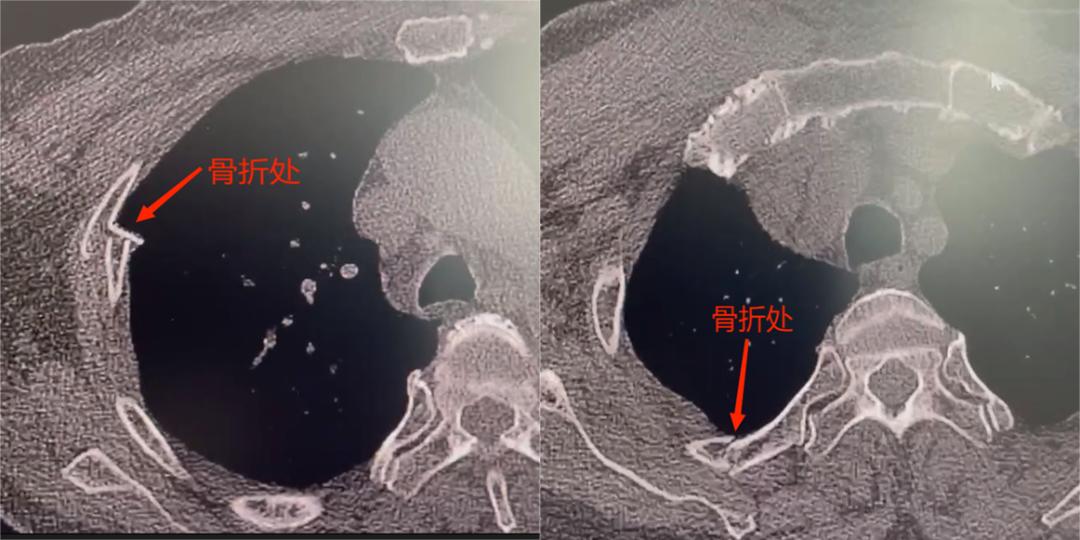

影像学提示,患者右侧多根肋骨骨折、肺挫伤、胸腔积血。患者既往有脑梗后遗症引起的右侧肢体偏瘫,肌力3级,合并胸外伤后破坏了胸廓结构稳定性,疼痛又增加了患者自主咳嗽排痰的难度,从而逐渐出现胸闷、气促等症状。此时,若不及时进行手术治疗,患者肺部感染将紧随而来,可能危及生命。

胸外科唐剑锋主任团队在评估后认为及时手术固定肋骨骨折恢复胸廓完整性对改善患者呼吸功能有巨大帮助,综合考虑后决定实施全胸腔镜下肋骨骨折复位内固定手术。手术仅需在患者胸壁建立1个1cm的观察孔,2个3cm的操作孔就能同时完成前、后段肋骨骨折内固定手术。术后患者疼痛明显减轻,咳痰与呼吸困难明显缓解。

唐主任介绍,该患者属于2-4肋前段及后段的高位肋骨骨折,目前主流术式是用20-30cm的大切口兼顾到多段肋骨骨折的复位内固定术,若术中再切开、切断部分肌肉无疑是对这名脑梗后伴右侧肢体运动障碍患者呼吸功能的二次损伤。全胸腔镜下肋骨骨折复位内固定手术避免了传统大切口的同时,保留了肌肉结构完整性,更有助于术后呼吸功能的迅速恢复,为胸部创伤的患者提供了新的选择。